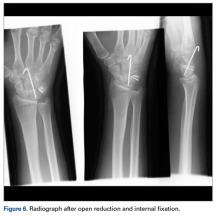

Later, however, the hand surgery team evaluated the radiograph as well as computed tomography (CT) scans and found a translunate, transradial, transtriquetral, transtrapezoid perilunate dislocation of the wrist with multiple metacarpal neck fractures ( Figures 1-5 ).The next day, with the patient under general anesthesia, an attempt to reduce the perilunate dislocation by manipulation was unsuccessful. Open reduction and internal fixation (ORIF) were performed through a dorsal approach; the perilunate dislocation was reduced and stabilized with lunocapitate 1.2-mm Kirschner wire (K-wire). The scapholunate and lunotriquetral ligaments were found to be intact, and the significantly displaced triquetral fracture was treated with internal fixation involving 2 minifragment screws ( Figure 6 ).

Perilunate injuries are classified as lesser arc injuries (purely ligamentous) or greater arc injuries (osseoligamentous). Greater arc injuries involve fracture of one or more carpal bones with associated ligamentous injuries. 3 The greater or lesser arc injuries described by Mayfield and colleagues 2 imply a specific pattern of force transmission with axial loading in a dorsiflexed and ulnar-deviated wrist with intercarpal supination. Graham 4 introduced a concept of inferior arc injury with the forces passing through the radiocarpal joint with fracture of the radial styloid or juxta-articular margin. Similarly, lunate fracture in perilunate dislocations was explained by Bain and colleagues 5 in the translunate arc concept in which forces pass through the lunate bone. A study involving a literature review of translunate perilunate dislocations noted associated transradial, trans-scaphoid, transcapitate, and transtriquetral fractures in order of decreasing frequency. 6 To our knowledge, no case of translunate perilunate dislocation with multiple carpal and metacarpal fractures with radial styloid fracture has been reported in the literature.

Our patient’s associated multiple metacarpal neck fractures can be explained by the peculiar double-impact injury with initial axial loading across the hyperextended metacarpophalangeal joint, followed by axial loading across the hyperextended and ulnar-deviated wrist, causing greater arc perilunate fracture-dislocation. The mechanism of lunate injury in this case seems to be longitudinal impaction of the capitate shearing against the volar lunate in the axial plane causing a volar lip fracture (Teisen type I), and this may be accentuated by tension in the volar radiolunate ligament. 6,7 Associated triquetral fracture in perilunate dislocation is well described in the literature. 6 However, the trapezoid fracture in our case implies a very atypical pattern of force transmission with the arc probably passing more distally through the trapezoid laterally and the triquetrum medially.